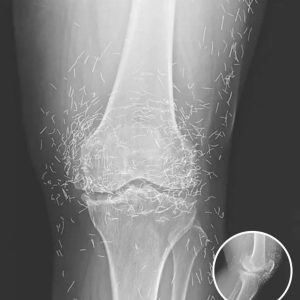

Doctors Stunned After Looking At This X-Ray Of Woman Suffering Joint Pain

A routine X-ray brought an unexpected discovery when doctors examined the knees of a 65-year-old woman with severe joint pain. Instead of typical signs of damage, they…